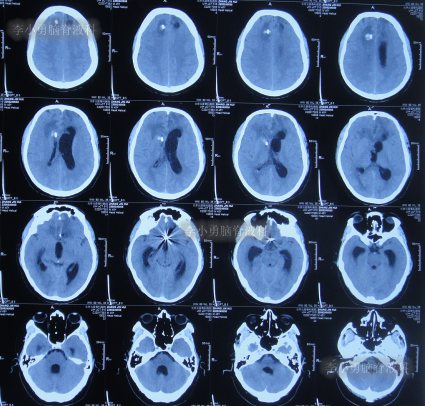

该院治疗20余天时间内,虽每天进行腰穿治疗,但期间3次查头颅CT均显示脑室持续的扩张(图-7、图-8、图-9)。

图-7:2022年8月9日头颅CT

图-8:2022年8月14日头颅CT

图-9:2022年8月15日头颅CT